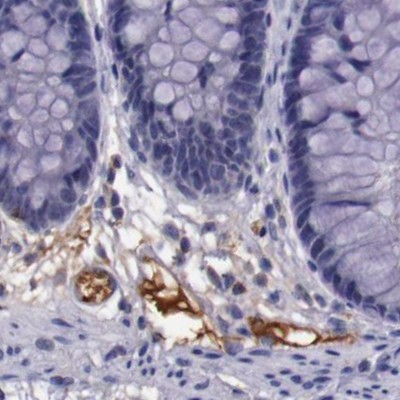

Immunohistochemical staining of human colon, kidney, lung and lymph node using Anti-APOH antibody HPA001654 (A) shows similar protein distribution across tissues to independent antibody HPA003732 (B).